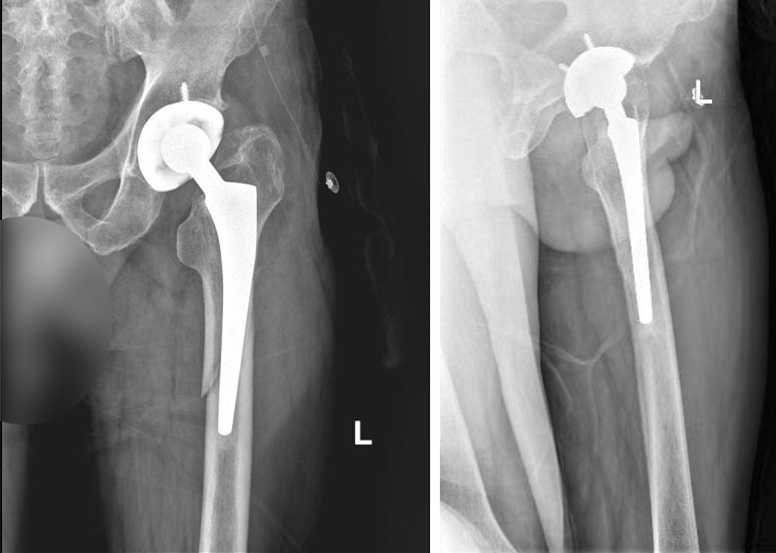

患者就诊时的正、侧位影像。